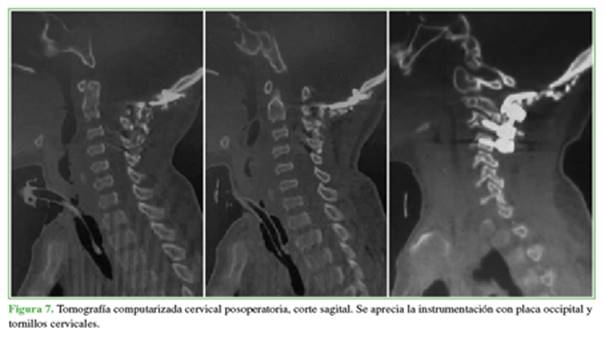

En el posoperatorio, se realizó una tomografía computarizada de control y se observó la descompresión con el material en la posición correcta (Figuras 7 y 8).